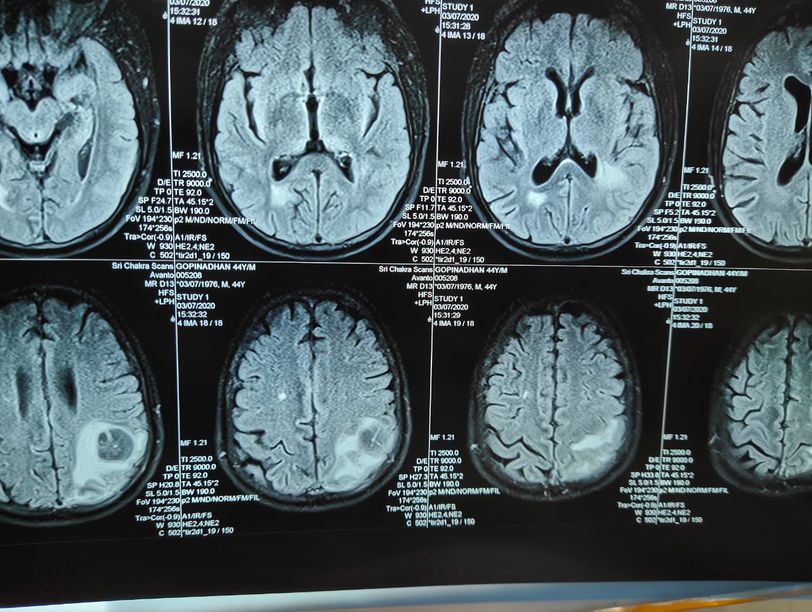

Diagnosis?

Brain infraction

Hemorrhage